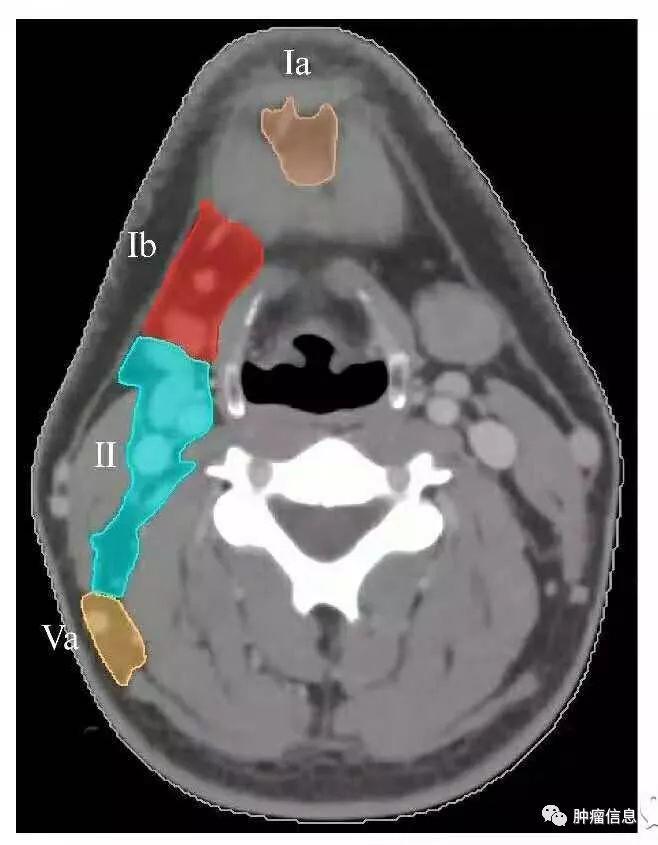

颈部I区淋巴结

上界:下颌舌骨肌下界:舌骨前界:下颌骨前缘后界:颌下腺后缘内侧界:二腹肌前腹外缘外侧界:下颌骨内侧缘IA:颏下淋巴结(前正中线至二腹肌前腹与舌骨下缘之间的区域)IB:颌下淋巴结(下颌骨上缘,二腹肌前腹与颌下腺后缘之间的区域)

颈部I区图中淡黄色为Ia图中红色为Ib

颈部II区淋巴结

上界:颅底下界:舌骨上缘前界:颌下腺后缘后界:胸锁乳突肌后缘内界:颈血管鞘内缘外侧界:胸锁乳突肌内缘IIA:颈动脉前区IIB:颈动脉后区

颈部II区图中绿色为II区

颈部V区淋巴结

上界:颅底下界:锁骨上缘前界:胸锁乳突肌后缘后界:斜方肌前缘VA:环状软骨下缘以上区域VB:环状软骨下缘至锁骨上缘区域

颈部V区图中黄色为V区